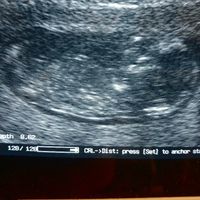

Ciao ragazze sono a 14 settimane, l altro ieri a 13+5 abbiamo fatto un eco di controllo ma la gine non si é sbilanciata... secondo voi maschio o femmina?

Mancano ancora tantissime settimane alla morfologica, che avrò il 15 Luglio, mi ritrovo spesso a fantasticare se sarà Filippo o Lucrezia, io mi sento maschio ma non si sa mai. Mi affido a voi esperte di Nub Theory, cosa dite maschio o femmina?? ...